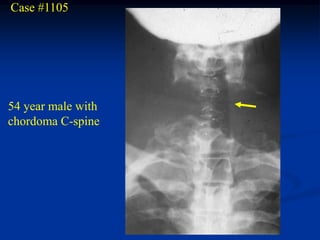

Case #1105

54 year male with

chordoma C-spine